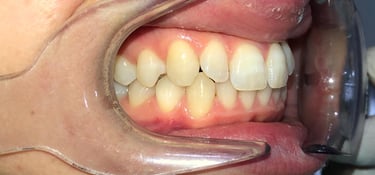

NUESTROS CASOS REALES